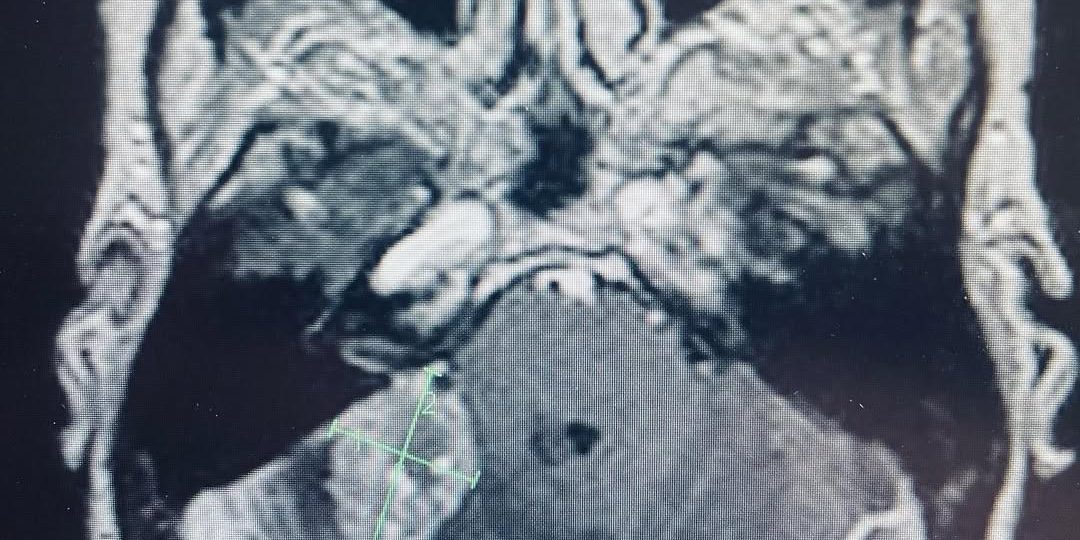

This female patient presented with dizziness and difficulty walking with a past history of colon cancer. Her brain MRI showed a metastatic tumor deep in her cerebellum. The pressure on the cerebellum was causing her balance issues. She had a craniotomy to remove the tumor. Microsurgery and stereotactic navigation were useful in this case given the tumor’s location deep in the brain. The tumor was completely removed (second picture, arrows), and her neurologic difficulties all resolved.